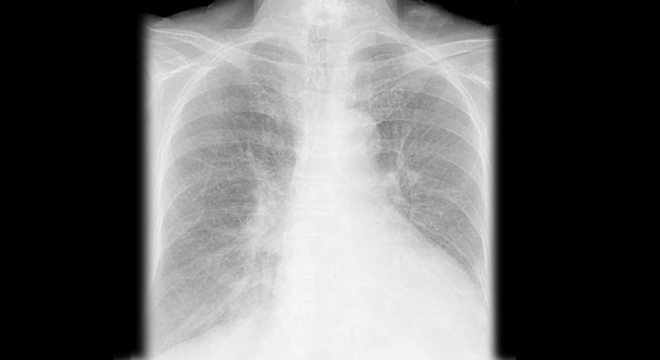

Lungenödem: Röntgenbild der Lunge

Anhand des klinischen Bildes mit den oben genannten Beschwerden stellt der Arzt das Lungenödem fest. Beim Abhören der Lunge mit dem Stethoskop (Auskultation) sind typische Atemgeräusche (sogenannte feuchte Rasselgeräusche) zu hören. Im Lungenröntgen sind Zeichen der Flüssigkeitsansammlung zu sehen. Die Blutgaswerte geben Aufschluss über das Ausmass des Sauerstoffmangels.